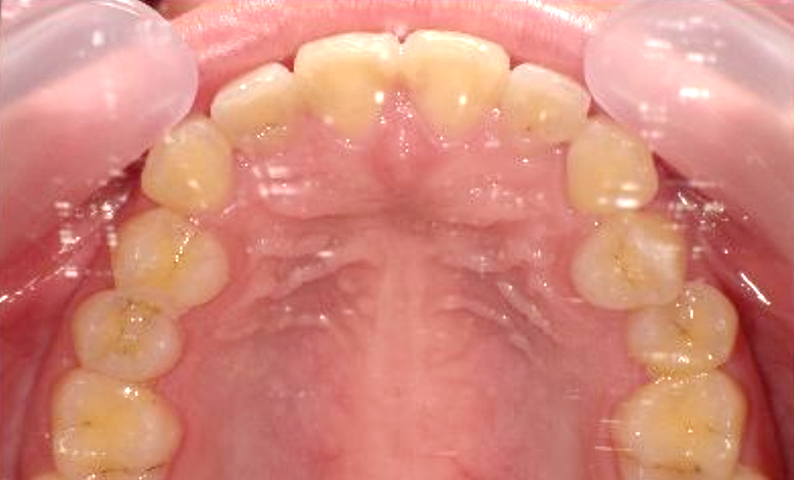

症例_007 前歯「捻転歯」症例

治療期間:10ヶ月金額:30万円+税20代女性少しのねじれ上の前歯だけ

| Before | After |